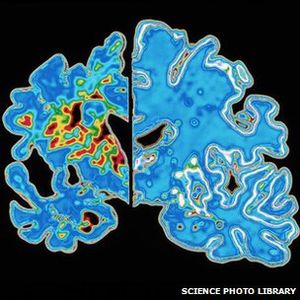

Alzheimer im Gehirn: immer mehr Erkrankungen (Foto: Science Foto Library) |